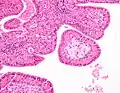

The appearance of this tumor under the microscope is unique. There are cystic spaces surrounded by two uniform rows of oncocytes, which are epithelial cells with abundant, granular, eosinophilic cytoplasm.[7] The cystic spaces have epithelium referred to as papillary infoldings that protrude into them. Additionally, the epithelium has lymphoid stroma with germinal center formation.

Low magnification micrograph of a Warthin tumor arising from the parotid gland. -

Histopathology of Warthin tumor in the parotid gland. H&E stain. -